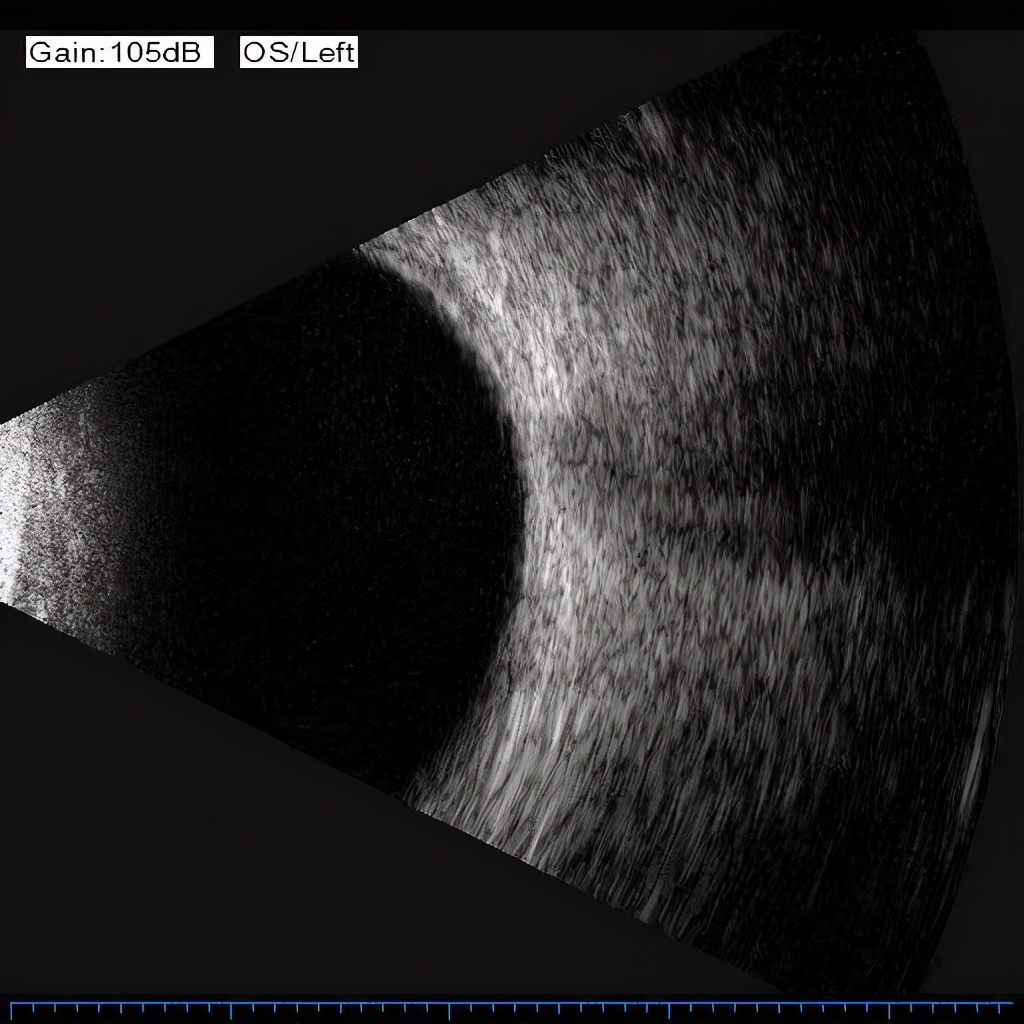

杜磊副教授在显微镜下气定神闲、精雕细刻的处理每一个细节,在“黑科技”助阵下,成功实施“左眼后入路玻璃体切割术+增殖膜剥除+眼内光凝+注气术”。不到50分钟,就将刘先生左眼的玻璃体积血及增殖完全清除。术后检查显示,刘先生眼压较术前无明显波动,未出现其他并发症状;术后第二天,左眼出血已完全清除;术后第三天,视力已有明显好转。3月20日复查显示,其视力已奇迹般恢复到0.8。

经历两次惊心动魄手术的刘先生感慨万千,他也是湖北首个玻切微创治疗“提速”体验者。杜磊副教授介绍,与常规眼底手术最高切速仅为每分钟5000-7500次相比,此次手术切割速率达到每分钟1万次,不仅大大缩短了手术时间,还明显减少了对眼睛“底片”——视网膜的牵拉,能更快液化玻璃体,增加了抽吸流速。同时,斜面切头能更加贴近视网膜进行精细化操作,更好地处理细小增生组织,大大提升了手术效率,缓解了术中病人的紧张情绪,优化了就医体验。